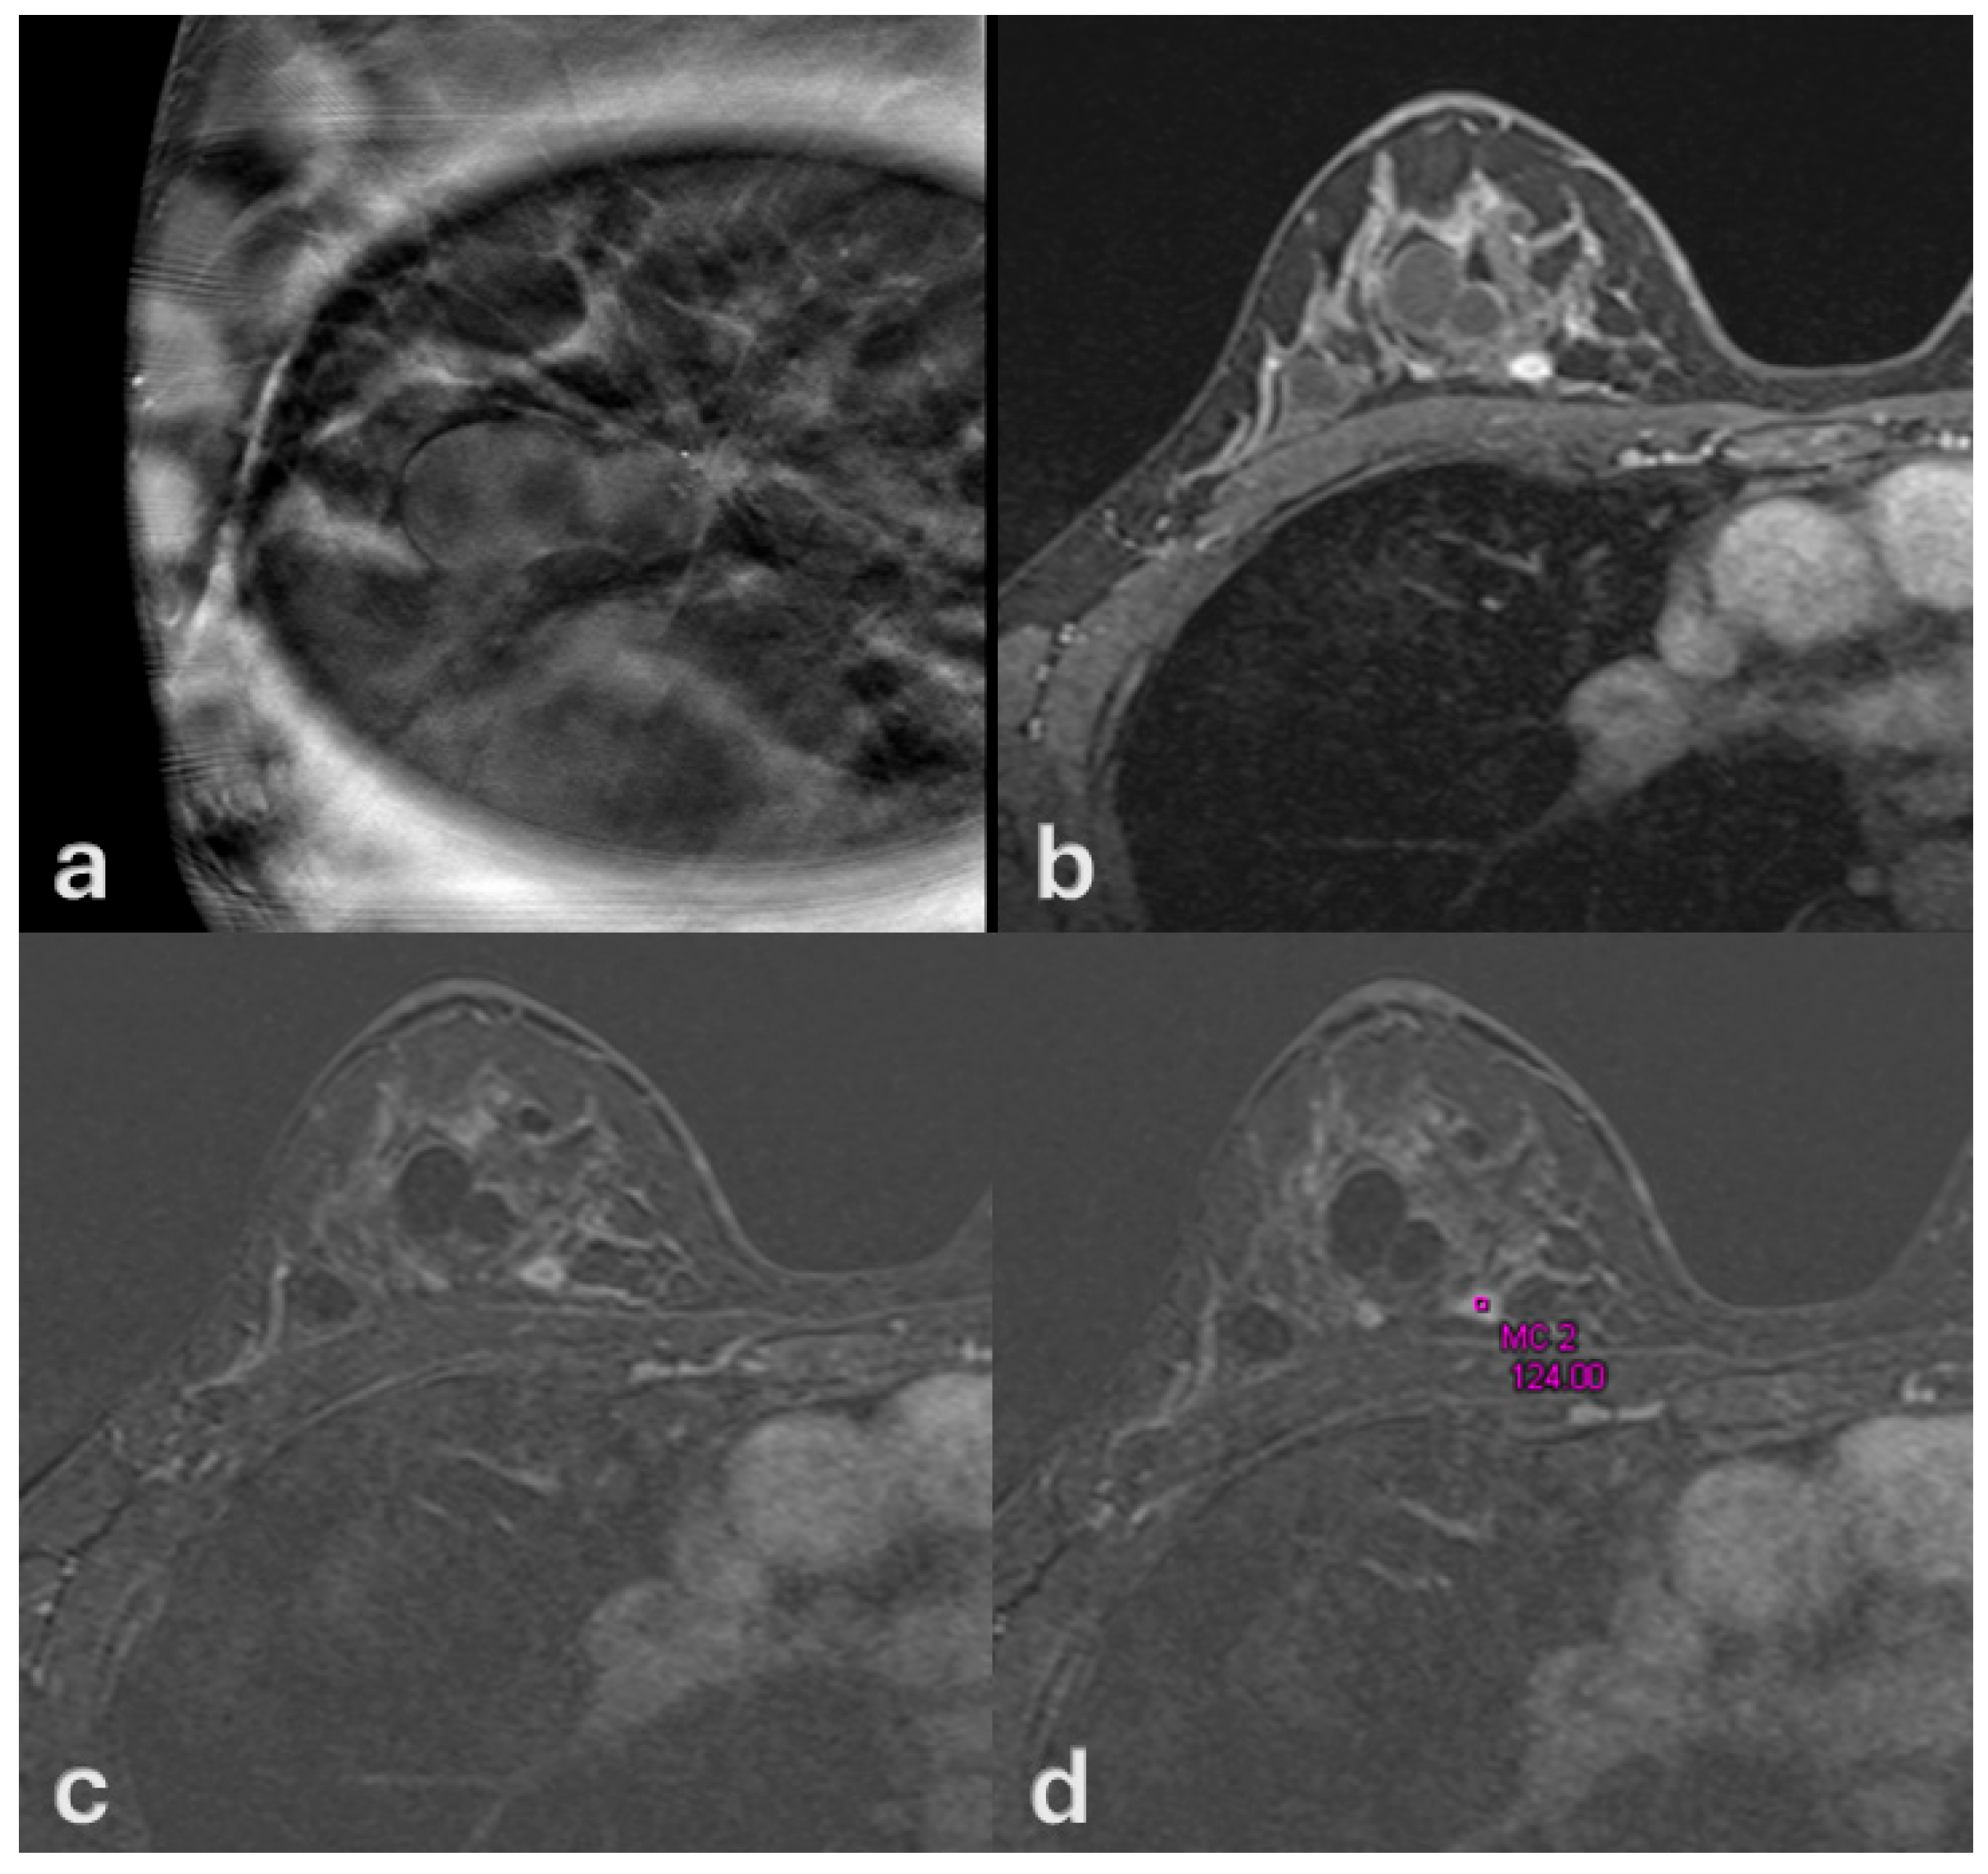

Multimodal Imaging of Ductal Carcinoma In Situ: A Single-Center Study of 75 Cases

3. Results